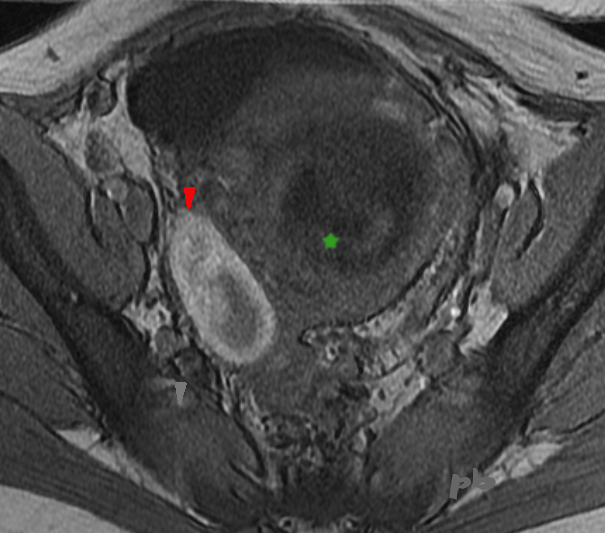

IRM axial T1

10 mois plus tard.

On retrouve la composante hémorragique du kyste ovarien gauche, en hypersignal T1, avec des végétations plus exubérantes.

Une biopsie péritonéale a pu être réalisée, confirmant l’adénocarcinome très probablement d’origine ovarienne.

Ce dossier permet de rappeler le lien qui existe entre endométriose et certains types de cancers ovariens, endométrioïdes en particulier.